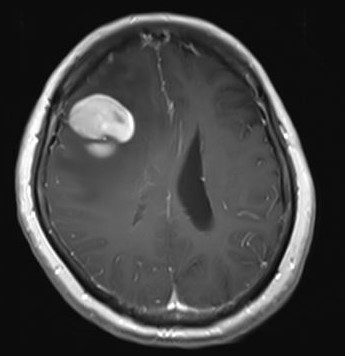

中枢神経系原発悪性リンパ腫のMRI

6割以上が大脳に発生し、脳の圧迫症状(巣症状と言います)で様々な症状を起こします。初発症状としては、腫瘍の発生した場所に応じた脳局所症状(麻痺、失語、視力障害など)が半数近くに、頭蓋内圧亢進症状(頭痛、嘔気、嘔吐など)が1/3程度にみられます。また頻度は5%未満と少ないのですが、目のぶどう膜炎を併発することが特徴的です。